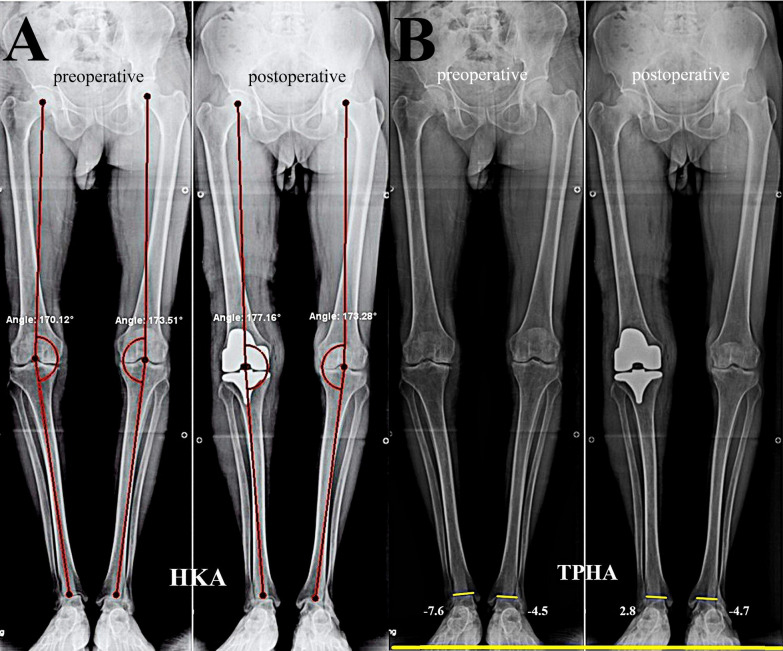

Methods: This retrospective cohort study included 70 patients with a mean age of 61.76 ± 5.96 years. The lower limb alignment was evaluated using the hip-knee-ankle (HKA) angle, while the AJLO was assessed using the tibial plafond to horizontal line angle (TPHA). The functional outcomes for side A were evaluated at a median follow-up of 18 (interquartile range (IQR): 12-46.2) months using the Knee Injury and Osteoarthritis Outcome Score (KOOS) and The American Orthopaedic Foot and Ankle Society (AOFAS) score for the knee and ankle joints, respectively.

Results: In side A, the HKA significantly improved from 167.49 ± 6.25 to 177.08 ± 4.39 (p < 0.001). No difference in AJLO was found between both sides preoperatively (p = 0.329). At the last follow-up, in side A, the AJLO changed significantly into less varus from -7.11 ± 5.44° to -1.10 ± 4.91° (p < 0.001); in side B, the AJLO showed no significant changes (-6.38 ± 6.10° versus -6.65 ± 6.50°, p = 0.970). For side A, the KOOS and AOFAS showed significant improvement, 45.20 ± 14.94 versus 75.72 ± 13.28 (p < 0.001) and 70 (65-75) versus 90 (80-90; p < 0.001), respectively. The preoperative HKA and AJLO on side A and side B showed significant positive correlations (r = 0.591, p < 0.001 and r = 0.611, p < 0.001, respectively). On side A, the postoperative HKA and AJLO showed a significant positive correlation (r = 0.298, p = 0.012). The preoperative and postoperative AJLO and AOFAS on side A showed nonsignificant negative correlations (r = -0.202, p = 0.277 and r = -0.115, p = 0.537, respectively). The preoperative and postoperative HKA and AOFAS on side A showed nonsignificant positive correlations (r = 0.126, p = 0.499 and r = 0.331, p = 0.069, respectively). The linear regression analysis indicated that for every 1° correction in HKA, the AJLO changed by 0.5° (R2 = 0.241, 95% confidence interval (CI) 0.298-0.747, p < 0.001).

Conclusions: The ipsilateral ankle joint realigned to a less varus position after ipsilateral TKA for managing knee OA with varus deformity, with an estimated half a degree of less varus AJLO after HKA correction by a degree. No changes occurred in the contralateral ankle joint. The ankle joint function improvement was not correlated to the HKA or AJLO changes.